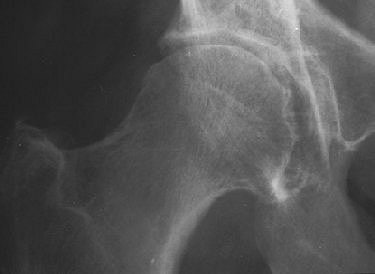

| Rapidly destructive hip osteoarthritis in 68-year-old woman with right-sided hip pain. Anteroposterior radiograph obtained at onset of symptoms shows moderate superolateral joint-space narrowing and small subchondral cystic lesion in acetabulum. Boutry N, Paul C, Leroy X, Fredoux D, Migaud H, Cotton A, "Rapidly Destructive Osteoarthritis of the Hip: MR Imaging Findings" (AJR 2002; 179:657-663). |

For JSN, weight bearing is an important component of x-ray evaluation, especially in the hips and knees. As a result, the standard patient position has been standing and bilateral weight bearing, but this protocol does benefit from refinement. Cibere suggested that in hip OA, the oblique standing view offers a better view of JSN. In knee OA, she endorsed the semiflexed view, which brings more of the posterior femoral condyle into the picture.